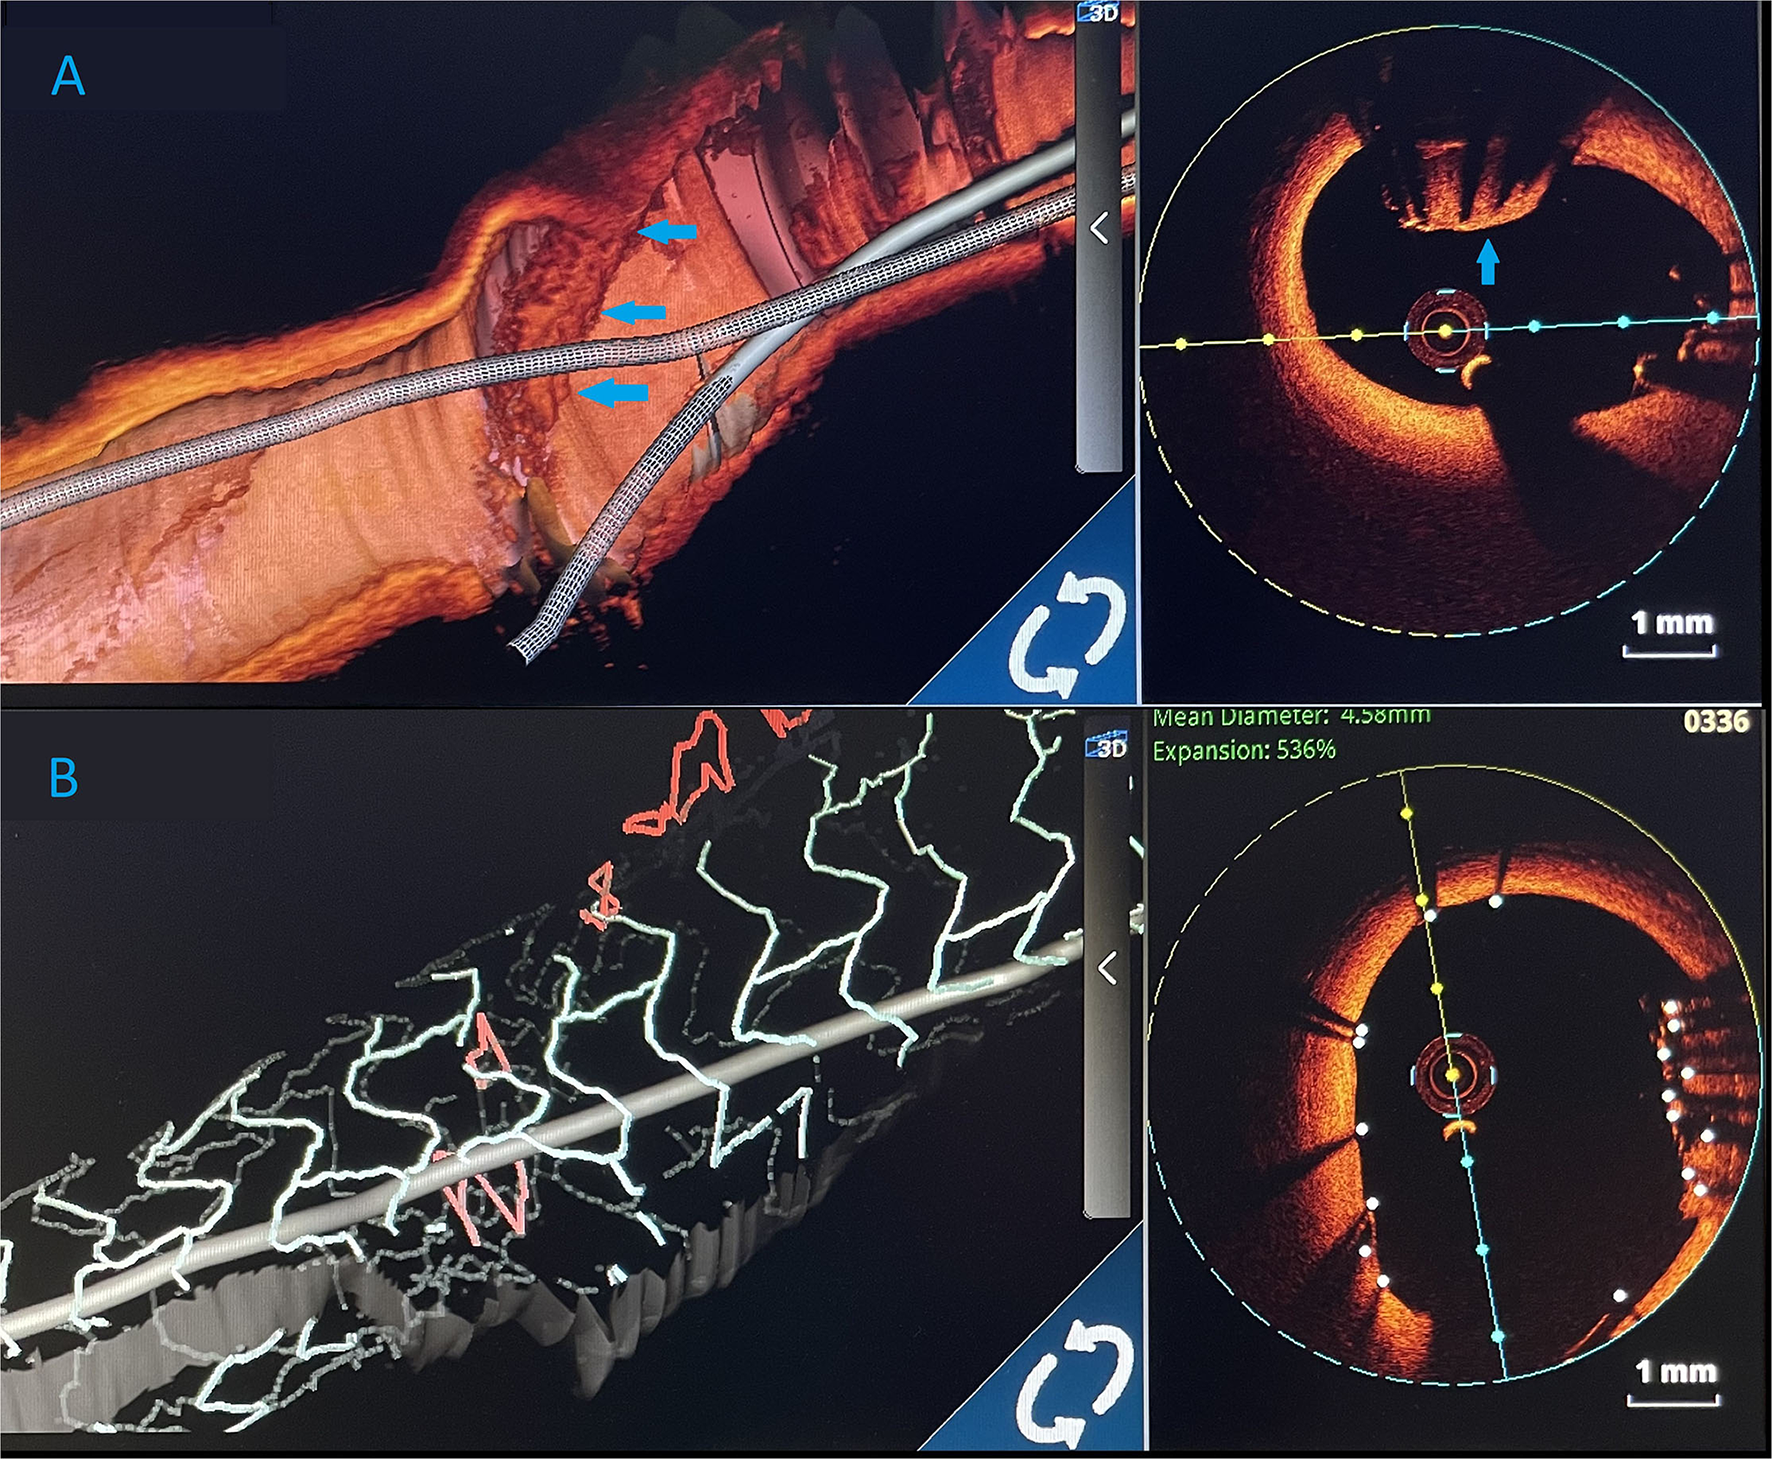

Figure 3

(A) Optical coherence tomography (OCT) finding an undeployed part of the lost stent in the left main artery. There are no signs of thrombosis around the stent. Below is the longitudinal view of the left main OCT. *Wire artifacts. (B) Optical coherence tomography image. Partially endothelialised (arrow) part of the undeployed stent in the LM. (C) OCT showing good apposition of the new stent and a successfully crushed part of the undeployed stent. Arrow indicating a single non fully apposed strut.

The procedure was finalized with a proximal optimisation technique (POT) in LMCA with an NC balloon (Quantum 4.5 × 8 mm, Boston Scientific). Final angiography showed TIMI III flow (Figure 4) and OCT demonstrated well-apposed stent struts with a crushed lost stent in LMCA (Figure 3C; Supplementary Video with final OCT pullback from LAD to LM). The patient had an uneventful recovery and is still in follow-up. Dual antiplatelet therapy with ticagrelor (90 mg two times daily) and acetylsalicylic acid (100 mg one time daily) was continued for 12 months after the intervention. Currently, the patient is prescribed ticagrelor (60 mg two times daily) together with acetylsalicylic acid (100 mg once daily) for an additional 12 months. Afterwards, the plan is to recommend acetylsalicylic acid lifelong (100 mg once daily) and a vascular dose of rivaroxaban (2.5 mg two times daily).

Figure 4

Three-dimensional (3D) images. (A) 3D render of an optical coherence tomography (OCT) showing an undeployed lost stent (blue arrows) in the left main artery. (B) Optical coherence tomography 3D view. After LM stent implantation, lost stent (blue arrows) is successfully crushed against the left main artery wall.